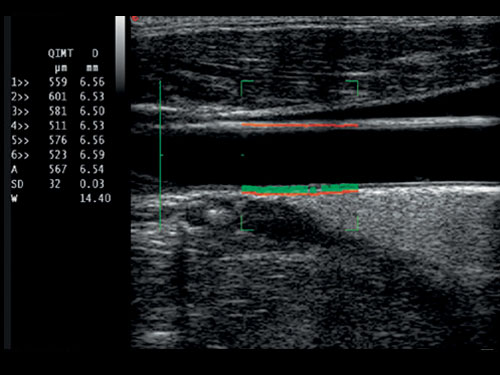

QIMT: Automatická detekce tloušťky média Intima v reálném čase, včetně směrodatné odchylky a indexu spolehlivosti, na základě analýzy RF signálu.